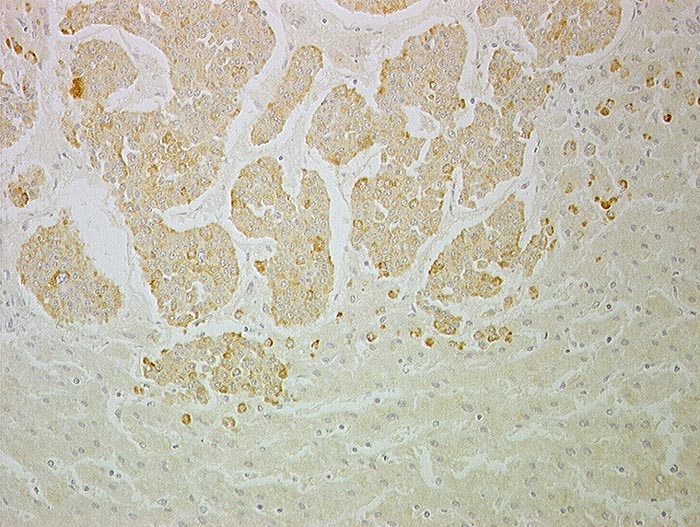

AP/ Lebermetastase: Neuroendokrines Karzinom

Lebermetastase: Neuroendokrines Karzinom

Leber